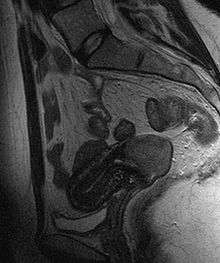

Often before the biopsy, the doctor asks for medical imaging to rule out other causes of woman's symptoms. Imaging modalities such as ultrasound, CT scan and MRI have been used to look for alternating disease, spread of tumor and effect on adjacent structures. Typically, they appear as heterogeneous mass in the cervix.[37]